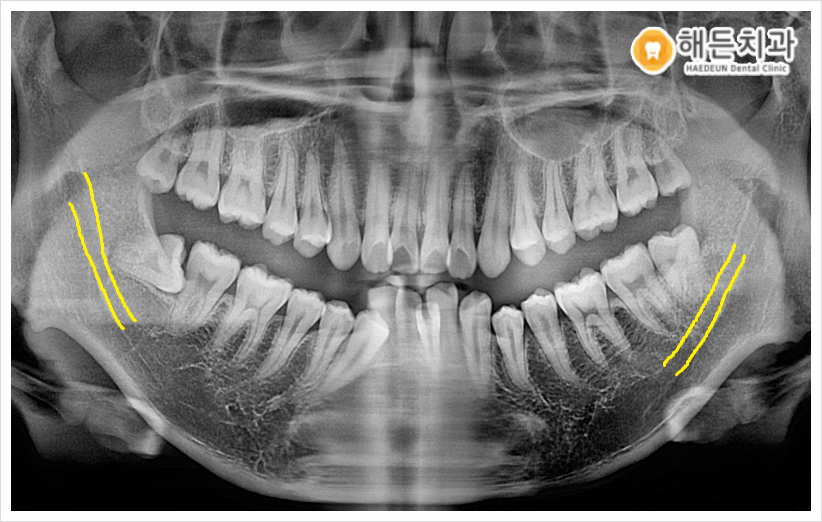

그리고 파노라마 사진상에서 아래턱 하방으로 지나가는 하치조 신경과 사랑니가 인접해 있는 것을 확인할 수 있었는데요.

발치 시 하치조 신경을 건들게 되면 신경 손상의 위험이 있어 일시적 혹은 영구적으로 감각 이상을 초래할 수 있고, 근육 움직임이 이상해지는 등 부작용이 생길 수 있기 때문에 발치 시 주의가 필요한 케이스였습니다.

저희 천안아산치과 해든에서는 풍부한 사랑니 발치 노하우를 갖고 있는 대표 원장님께서 발치 전 CT 촬영을 통해 사랑니의 위치, 신경과의 거리, 인접 구조물과의 거리 등을 정밀하고 꼼꼼하게 체크한 후에 안정적으로 발치를 진행하였습니다!